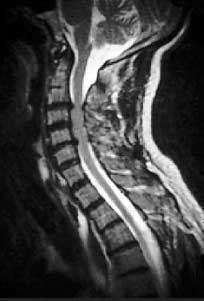

Магнитно-резонансная томография (МРТ) является одним из самых современных методов исследования, помогающим точно установить уровень и тяжесть поражения суставов при ОА [4]. Данная методика обладает целым рядом достоинств: хорошее контрастирование мягких тканей, свободный выбор плоскости изображения, трехмерный характер получаемой информации, отсутствие лучевой нагрузки и артефактов от костных структур, воздуха. МРТ обеспечивает контрастность в изображении хрящевого слоя, позволяет идентифицировать поверхностные изменения различных размеров и отклонения в обмене веществ (рис. 1).

Рис. 1

Рис. 1. Спондилоартроз. Стеноз позвоночного канала из-за протрузии межпозвонкового диска в шейном отделе позвоночника (МРТ)

У большинства пациентов со спондилоартрозом, даже при умеренной его симптоматике, при МРТ и компьютерной томографии обнаруживаются значительные дегенеративные изменения фасеточных суставов. Остеоартроз фасеточных суставов может способствовать развитию стеноза позвоночного канала и компрессиинервных корешков (рис. 2). В этом случае могут появиться симптомы люмбоишиалгии, такие как боль, онемение и слабость в ноге [1].